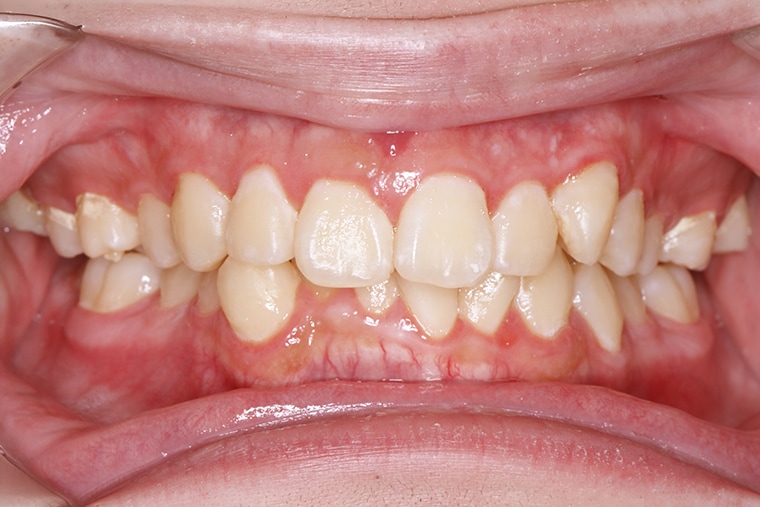

BEFORE

AFTER